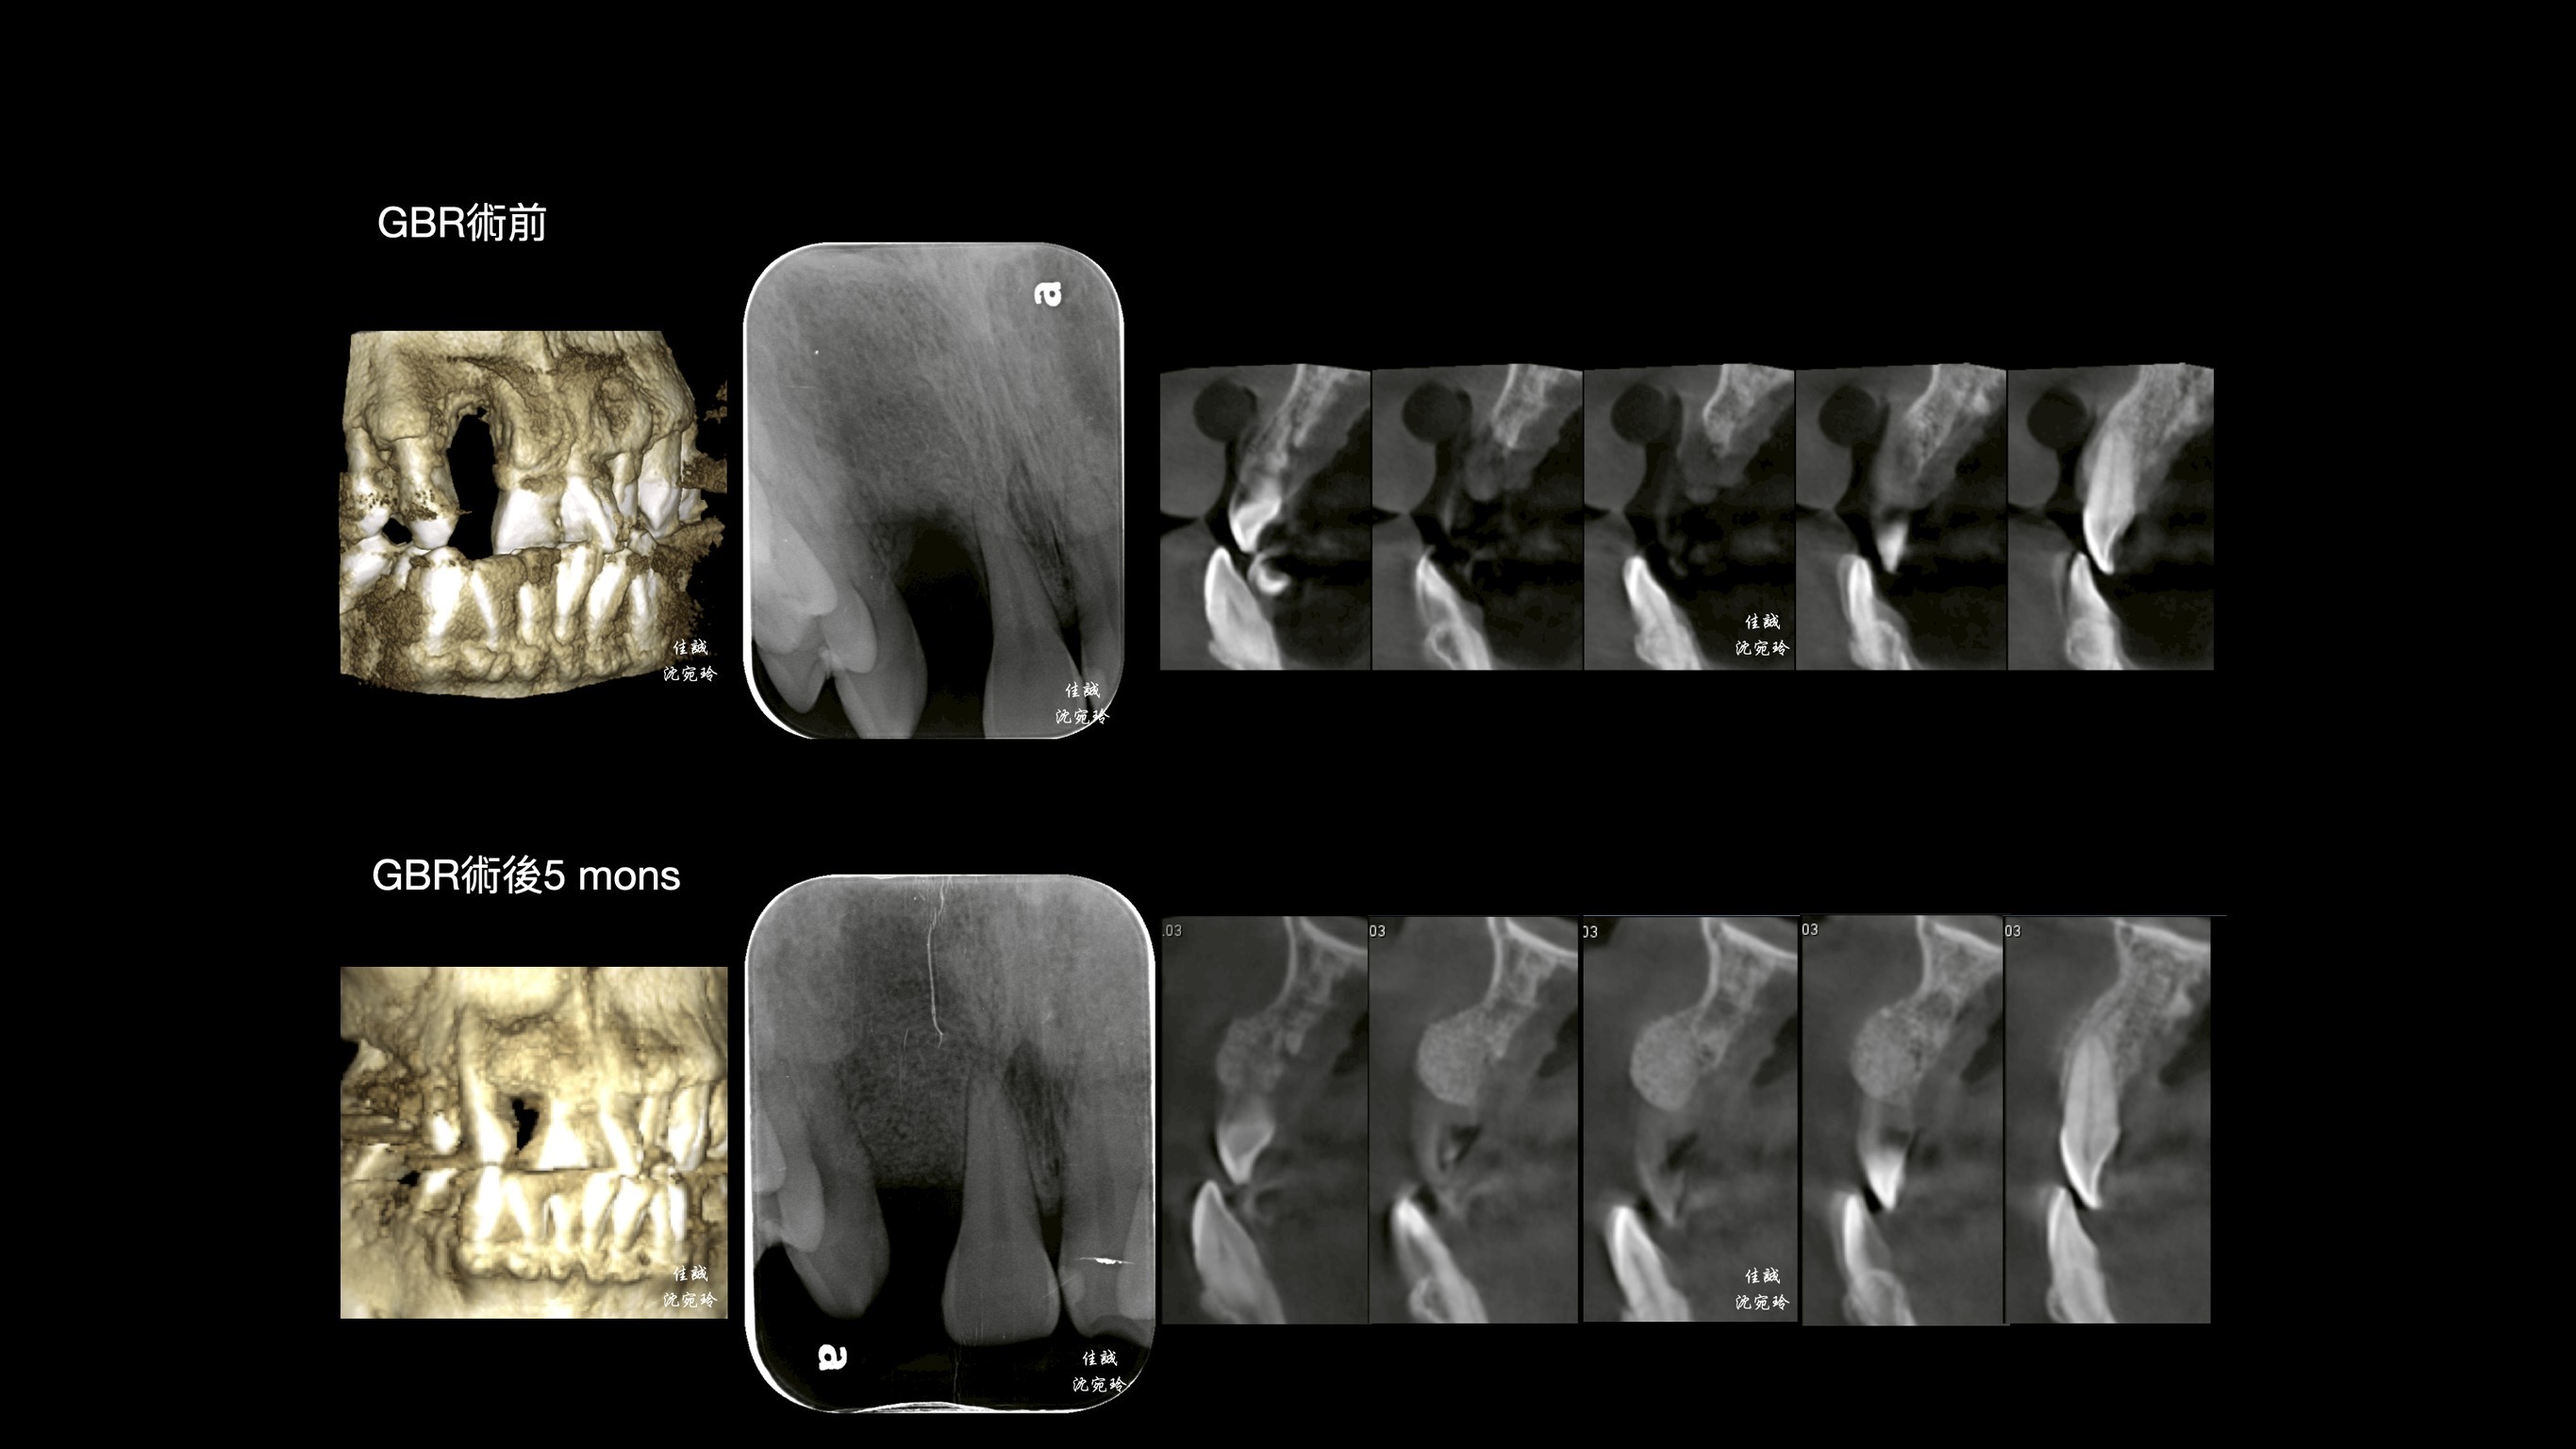

感謝醫師轉診,C先生自述右上側門牙因牙周病太搖而自行掉落,上前來「評估缺牙區可否植牙或是假牙?」

由於骨缺損程度大,此區若直接做假牙除了會塞食物,也不美觀。另外,做牙橋會犧牲太多齒質,需要根管治療;而馬里蘭牙橋做在平行度不佳的前後牙齒上面,也需要修磨較多,使用年限也不高;加上咬合排列不正,建議先做補骨手術,再接著做矯正治療,等矯正完成後,才做植牙或假牙的選擇。

手術挑戰是術區牙齦皮薄、骨缺損大,加上病患希望矯正前只開一次手術,對於方便矯正的接續進行,這次只補FDBA和 OSSIX plus。因為預期將來會吸收一些,我盡量補oversize,最後選在牙齒掉落後的三個月進場,增加贏面。

幾個月後,也仰賴病患體氣血循好,成果還不錯唷。